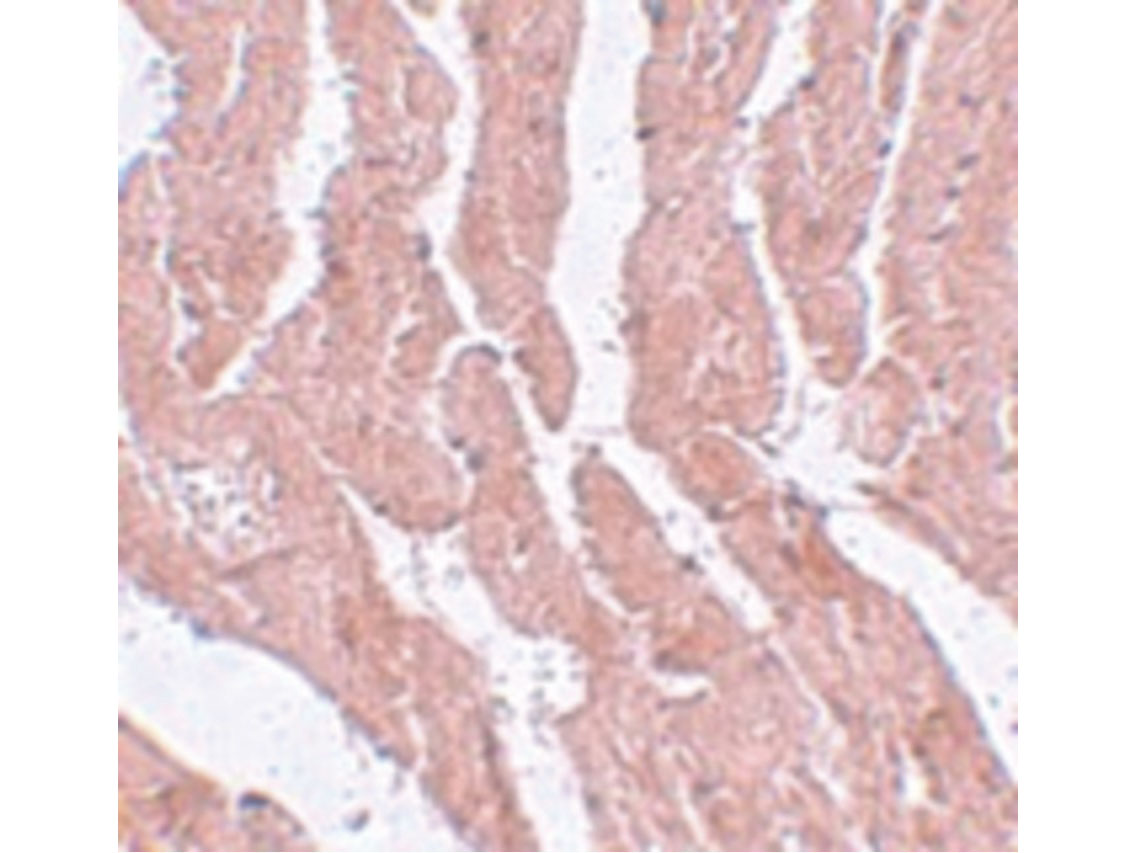

Anti-LZTR1 Antibody was affinity purified from monospecific antiserum by immunoaffinity chromatography. Cross reactivity with LZTR1 from other sources has not been determined. Protein function: Probable transcriptional regulator that may play a crucial role in embryogenesis. [The UniProt Consortium]

| Application: | ELISA, IHC, WB |

| Species reactivity: | human, mouse, rat |

| Immunogen: | 14 amino acid synthetic peptide near the N-terminus of human LZTR1. |